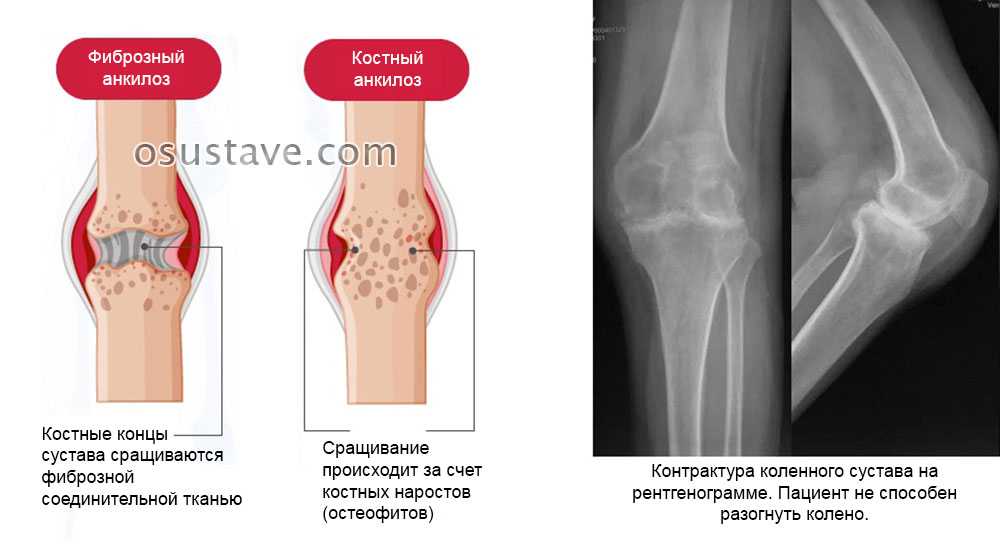

Рентгеновские снимки анкилоза суставов: Как это выглядит